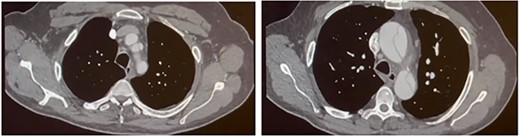

Four months later, the patient developed dyspnoea and orthopnoea. He was also found to be positive for COVID-19. He was clinically well and his hepatitis C viral load was undetectable. A CT aorta-thorax demonstrated that the ascending aorta had further dilated (60 × 61 mm). This aneurysm compressed the trachea resulting in his acute respiratory symptoms (Fig. 3). The patient was diagnosed with an acute-on-chronic type A aortic dissection with mild–moderate aortic regurgitation. Emergency thoracic aortic surgery was performed with remodelling of the sinotubular junction with a prosthetic graft and aortic valve repair. The patient had a long post-operative recovery phase complicated primarily due to his COVID-19 diagnosis. He was discharged 43 days after his surgery.

CT aorta thorax on patient’s re-admission four months later. Ascending aortic aneurysm has increased in size (measuring 60 × 61 mm) compressing the trachea.